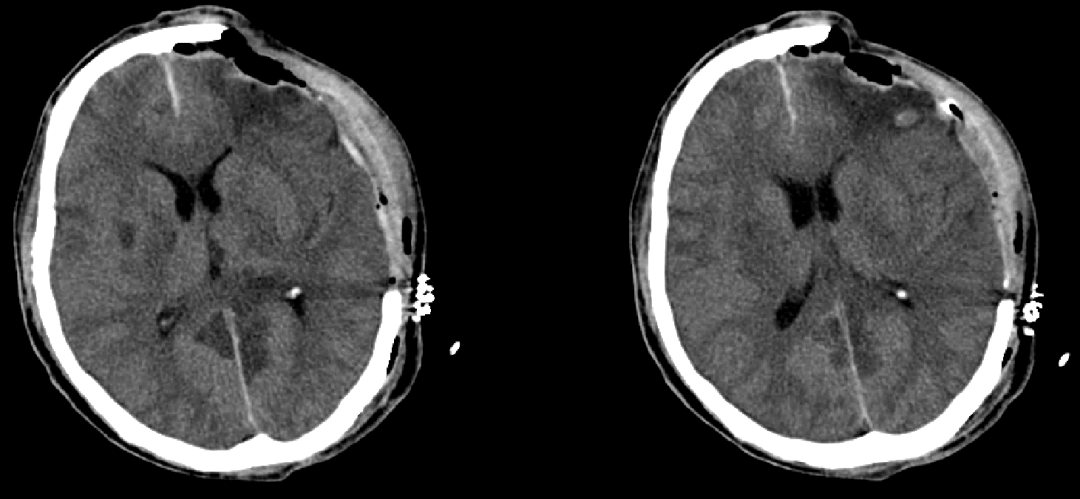

70歲的吳伯(化名)因骨質(zhì)疏松等原因不慎跌倒,當(dāng)時(shí)無昏迷,未及時(shí)就診。第二天清晨,患者出現(xiàn)頭痛難忍、嗜睡,家屬遂撥打了120,隨后送到惠州市第三人民醫(yī)院急診科。急診頭顱CT提示:大量硬膜下血腫。

患者術(shù)前CT,中線已偏移

患者病情越來越重,意識(shí)逐漸變差,惠州三院神經(jīng)外科團(tuán)隊(duì)及時(shí)為其行神經(jīng)內(nèi)鏡下“硬膜下血腫清除術(shù)”。在醫(yī)護(hù)團(tuán)隊(duì)的精心治療和護(hù)理下,吳伯最終順利康復(fù)出院!